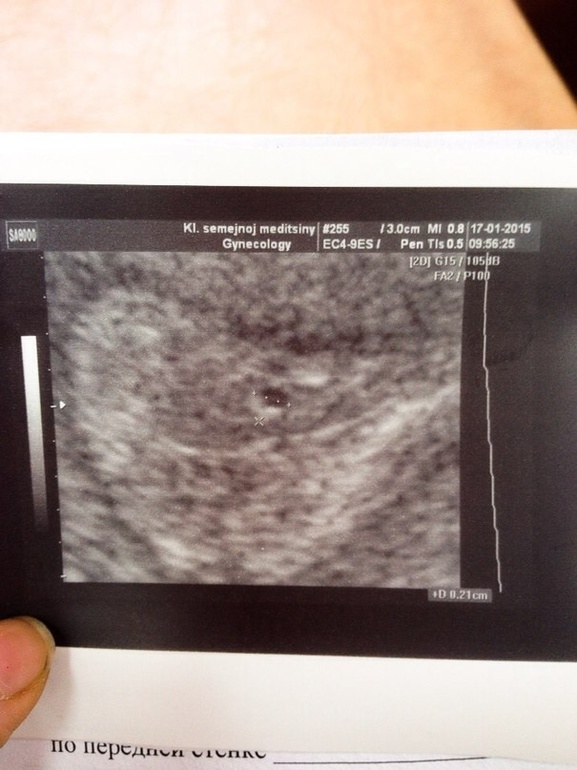

У меня все течты полосатые. И узист сказал, что это ни миома, ни полип.

К тому же пя видно только при хгч более 1500

А может это не пя?

У меня почти такое же было пя, даже вокруг так же все показывало не знаю как объяснить! Мне кажется это пя!

по узи кстати оч похоже на ПЯ.у Вас была поздняя О и вероятно прикрепление.поддержку зря отменили